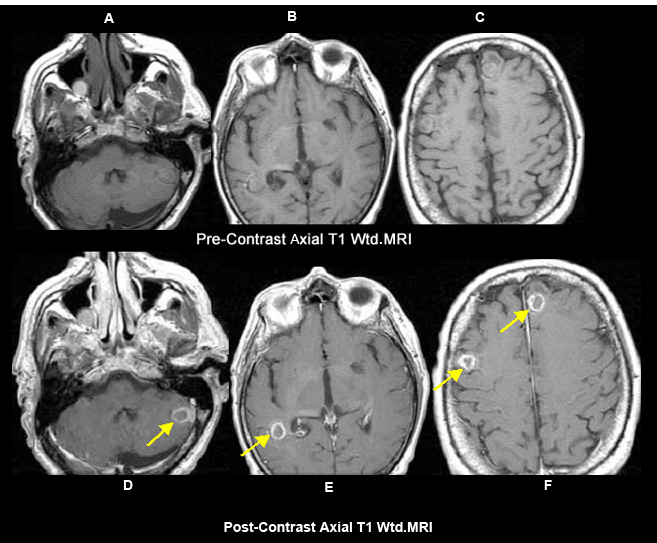

Figure 3

Fungal abscess - Non-Pyogenic abscess

Case 3

Imaging findings:

Figure 3 A, B, C: Pre-contrast axial T1 wtd. MRI

Figs 3 D, E, F: Post-contrast T1 wtd. MRI:

• Yellow arrow points to abscess cavity within the left cerebellar hemisphere (arrow in D), right posterior temporal lobe (arrow in E) and frontal lobes (arrows in F).

A case of fungal abscess in an immunocompromised patient.

Multiple enhancing ring lesions in an immunocompromised patient

Appropriate history and clinical findings are needed to aid in the etiology of abscess.